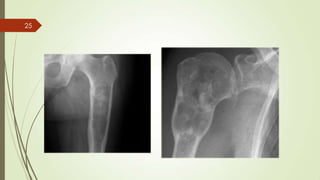

Imaging studies

 X ray : discrete calcification , appear large ,bony contour appears thinned and expanded .

 Periosteum overlying the tumor may be elevated.

 CT scan : detect subtle calcifications

 MRI : investigation of choice for assessing the extent of a chondrosarcoma.

 delineate the extent of soft-tissue involvement.

25